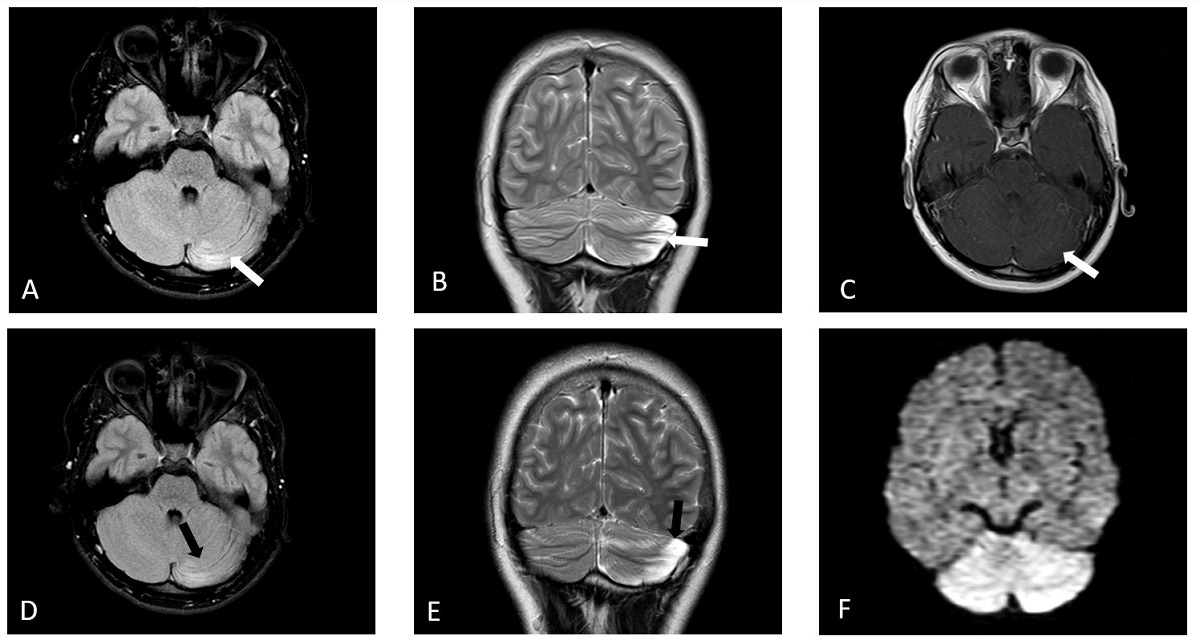

Paciente varón sin antecedentes personales ni familiares de interés. Con 14 años sufre un cuadro de CA, objetivable en las secuencias de resonancia magnética cerebral (RM), presentando atrofia crónica cerebelosa durante el seguimiento (Figs. 1 y 2). Poco después del debut, comienza con síntomas de inatención y disfunción ejecutiva, fluencia verbal lenta, dificultades visoespaciales, velocidad de procesamiento baja, mala regulación emocional y del comportamiento, cambios de humor, ansiedad obsesiva y pasividad. Los hallazgos cognitivos serán confirmados posteriormente en las pruebas neuropsicológicas. Con 21 años es diagnosticado de depresión mayor. La exploración muestra un paciente melancólico, con disminución del impulso vital, apatía, abulia y anhedonia. Refiere sentimientos de desesperanza y minusvalía. Presenta síndrome cerebeloso de predominio izquierdo (ataxia, dismetría, temblor postural, hipotonía y disdiadococinesia), que permite una marcha y manipulación funcionales; además de discurso bradilálico con aumento de latencia en las respuestas y baja velocidad de procesamiento. Realiza tratamiento psicológico y farmacológico con clonazepán, desvenlafaxina y olanzapina. Malos resultados con metilfenidato. El tratamiento añadido con lisdexanfetamina a 50 mg parece mejorar los síntomas de inatención y el paciente se siente más activo y con mayor fluidez para realizar las tareas.

| Figura 1. Cerebelitis aguda. Evolución de la afectación cerebelosa en el caso 1. (A) Axial FLAIR. (B) Coronal FSE T2. (C) Axial eco de gradiente T1 con contraste. Afectación difusa de folias cerebelosa y sustancia blanca en hemisferio cerebeloso izquierdo con hiperseñal en secuencia FLAIR y T2 y leve realce de las folias cerebelosas tras contraste que alcanza el vermis y presenta efecto de masa sobre el IV ventrículo (flechas blancas). Control a los 10 días. (D) Axial FLAIR. (E) Coronal FSE T2. (F) Axial eco de gradiente T1 con contraste. Marcada disminución de la afectación de hemisferio cerebeloso izquierdo que no presenta efecto de masa sobre el IV ventrículo ni realza tras contraste (flechas negras). |